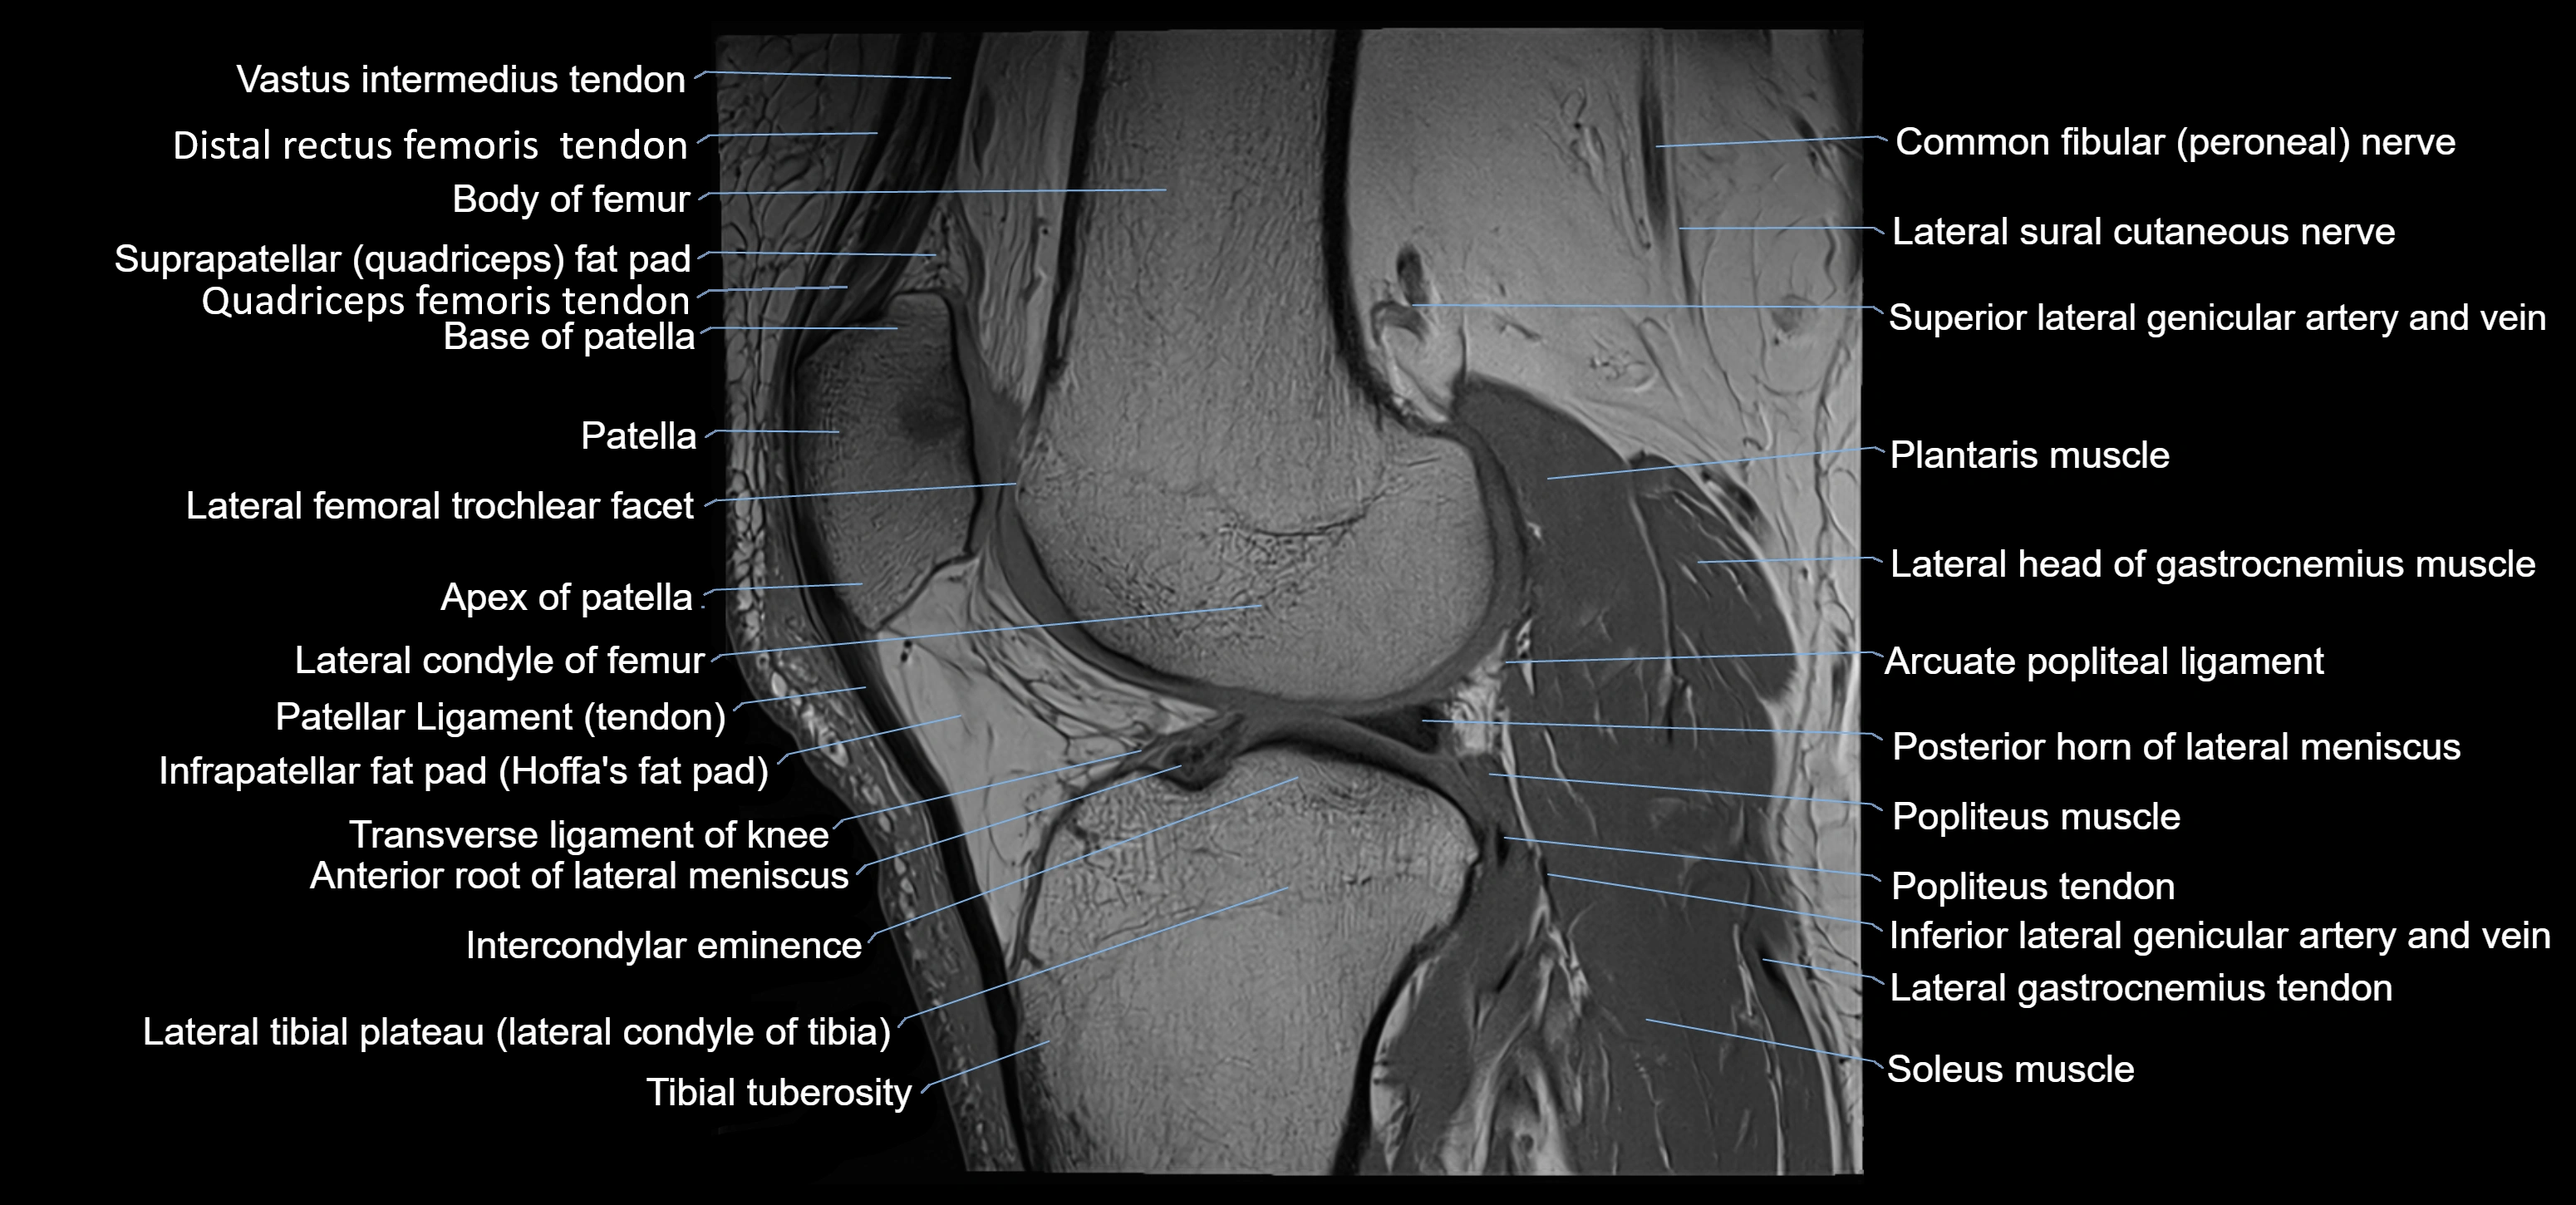

- Apex of patella

- Arcuate popliteal ligament

- Base of patella

- Body of femur

- Common fibular nerve

- Distal rectus femoris tendon

- Distal vastus intermedius tendon

- Infrapatellar fat pad

- Intercondylar eminence

- Lateral condyle of femur

- Lateral gastrocnemius tendon

- Lateral head of gastrocnemius muscle

- Lateral sural cutaneous nerve

- Lateral tibial plateau

- Patella

- Patellar tendon (patellar ligament)

- Plantaris muscle

- Popliteus muscle

- Popliteus tendon

- Posterior horn of lateral meniscus

- Soleus muscle

- Superior lateral genicular artery

- Superior lateral genicular vein

- Tibial tuberosity

- Transverse ligament of knee